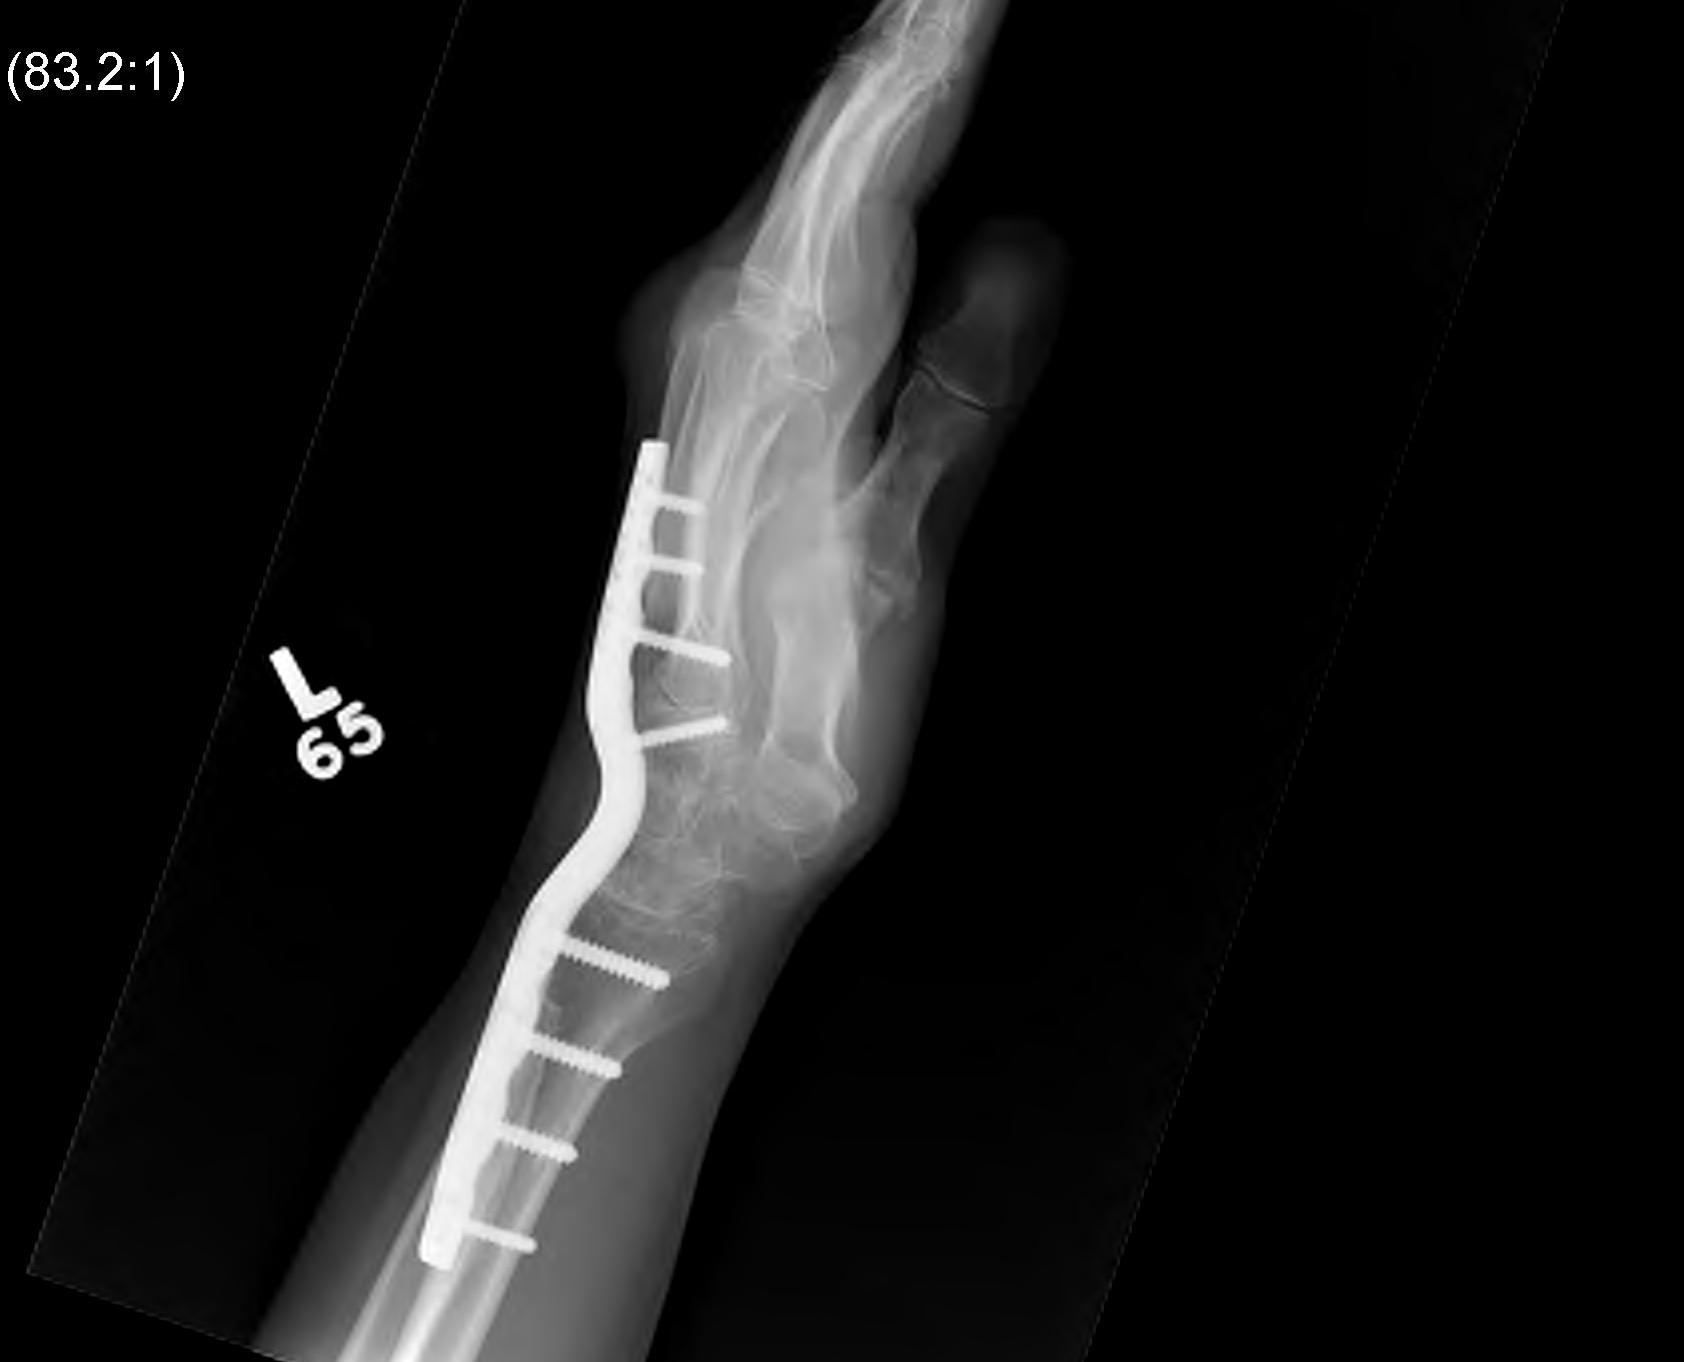

Total wrist arthrodesis

Indications

Diffuse advance radiocarpal and mid carpal OA

Poor bone stock

Stiff wrist

Loss of wrist extensors

High demand

Technique